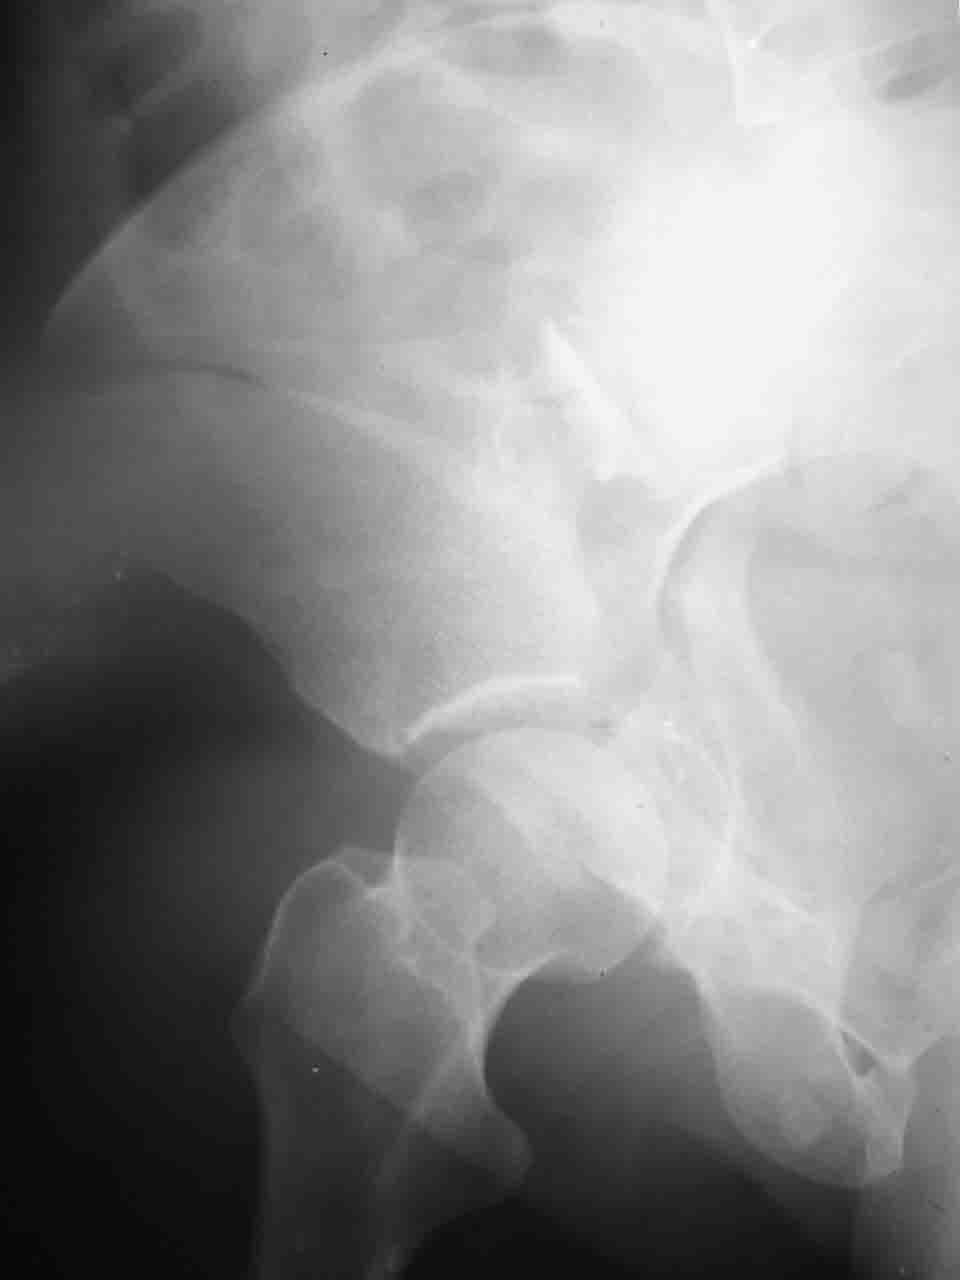

Логика подсказывает, что все-таки лучше иметь анатомически полноценную впадину, хотя ранее упоминалось состояние вторичной конгруэнтности и одно наблюдение у меня есть, когда у больного с полностью нарушенной анатомией впадины и подвывихом головки бедра кзади и кверху боли отсутствовали при относительно достаточном для стиля жизни больного объёме движений. Но это только одно наблюдение и кроме перелома впадины у этогобольного была и тяжелая ЧМТ в анамнезе. Основываясь на формулировке структуры ацетабулюм Э. Летурнеля - как перевернутой буквы Y, впадина для полноценной функции сустава должна иметь сферичность, соответствующую размеру головки бедра и если один из компонентов в дефиците, то функциональные последствия рано или поздно проявятся.

Сложностью, ассоциативностью характера перелома, я бы с радостью воспользовался мининвазивной перкутанной фиксацией винтами, но боюсь, что результат был бы ещё хуже, техникой непрямой репозиции перелома не владею, поэтому пытаясь получить анатомичную впадину приходится широко открывать, по крайней мере пока, а дальше буду пытаться уменьшать пространство...

> передним доступом на двухколонный перелом?

Илеофеморальный доступ не совсем передний и сравнительно с илеоингвинальным, и Кохера-Лангенбека открывает весь наружный таз кроме самых передних отделов лонных костей, фиксацию которых я не ставил в задачу. Обширность диссекции, большая длительность операции и более высокий риск гетерооссификации - отрицательные моменты в обмен на возможность легче ориентироваться.

Вопрос доступа к вертлужной впадине при остеосинтезе задача не простая. Конечно, у Летурнеля и Тайла всё давно описано, нам остается только брать на вооружение. Но сами понимаете, что не бывает двух одинаковых ситуаций, поэтому в каждом случае вопрос решается сугубо индивидуально. Наша главная цель - восстановить анатомию с нанесением минимальной дополнительной травмы тазобедреннному суставу, думаю с этим никто не поспорит. Расширенный илиофеморальный доступ уж слишком травматичен (как сказал один коллега "таз лежит отдельно, больной отдельно").Стоит ли делать из пациента анатомический препарат для того чтобы легче ориентироваться. Да и нужно ли собирать всю "мозаику"? Мы применяли при таких операциях своеобразную операционную хитрость - сначала устраняли грубое смещение крыла под гребнем с фиксацией так называемой "плавающей" пластиной (временно фиксированной на двух винтах)- доступ или продлевали боковой, или делали небольшой дополнительный разрез над гребнем. Это позволяло устранить грубое смещение и захождение отломков тела повздошной кости, что значительно облегчало репозицию и остеосинтез впадины над сводом. Основное внимание конечно же уделяли нагружаемому задне-верхнему отделу. Сообщите ваш адрес, пришлю схемы и рентгенограммы.